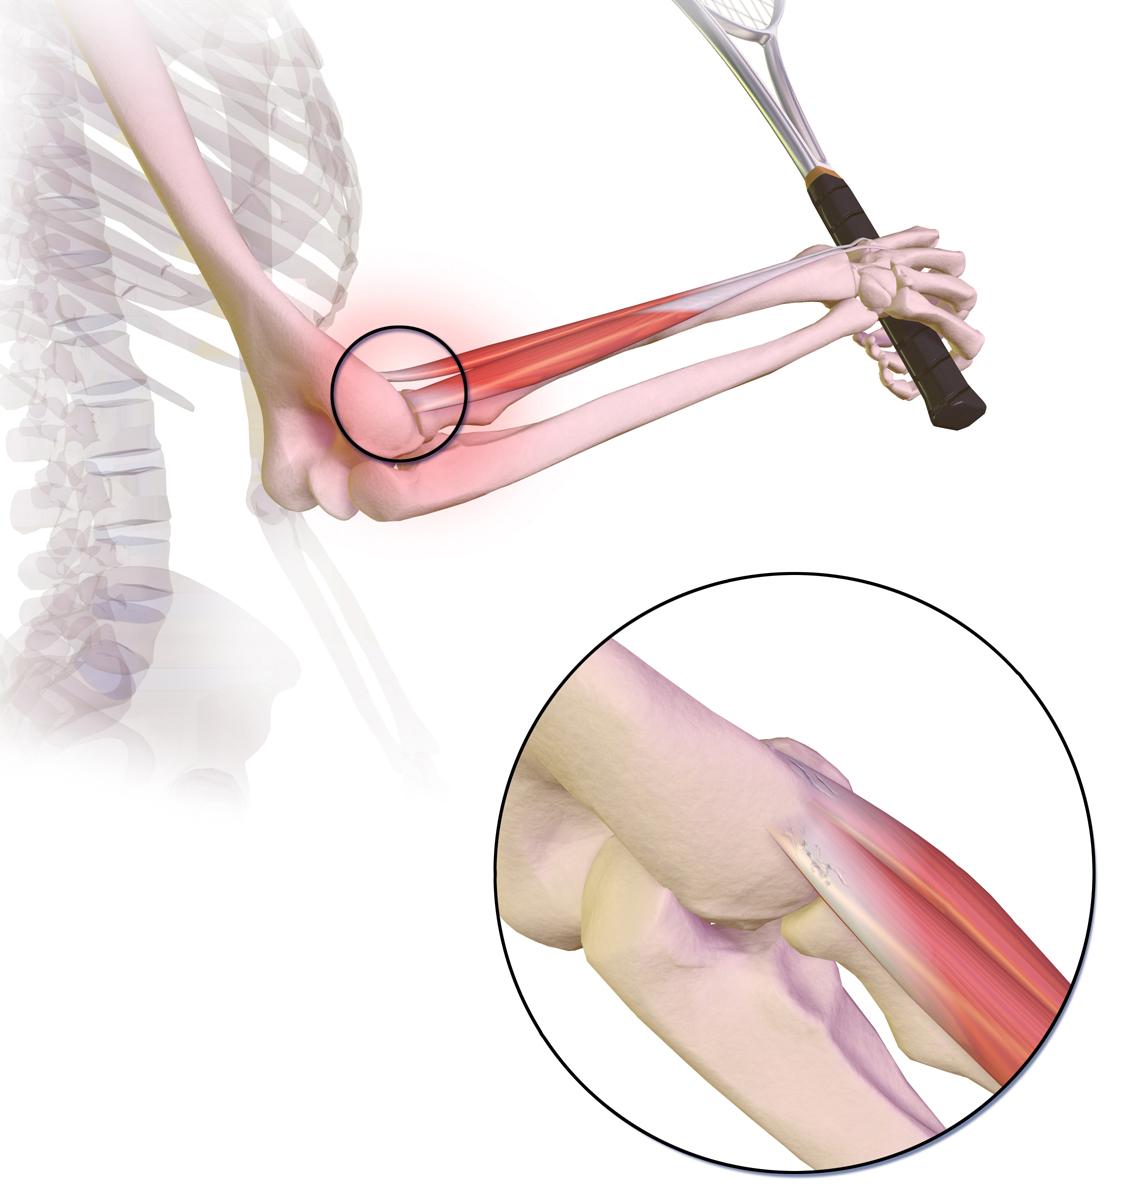

Coude de tennis

Le"tennis elbow" (le terme médical est épicondylite latérale) se produit lorsque les tendons de la surface extérieure du coude s'enflamment et deviennent douloureux.

Cette photo montre l'endroit où la douleur est ressentie, à l'extérieur du coude, dans le cas du tennis elbow :

© BruceBlaus, CC BY-SA 4.0, via Wikimedia Commons

Par BruceBlaus, CC BY-SA 4.0via Wikimedia Commons